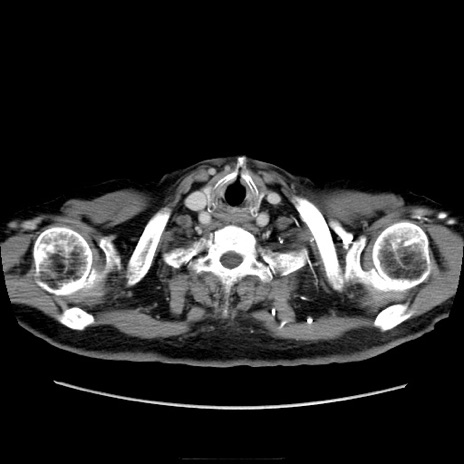

症例21(横断像)

【症例】70歳代男性

【主訴】腹痛

【現病歴】肝硬変・肝細胞癌にてかかりつけの方。約9時間前に食後より腹痛出現。症状が徐々に増悪し、嘔吐出現したため来院。

【既往歴】肝硬変、肝細胞癌(RFA、TACE後)

【身体所見】意識清明、表情苦悶様、BT 36℃、BP 129/78mmHg、P 88bpm、SpO2 97%(RA)、右上腹部から心窩部にかけて圧痛あり、反跳痛なし、筋性防御あり。

【データ】WBC 5800、CRP 0.16